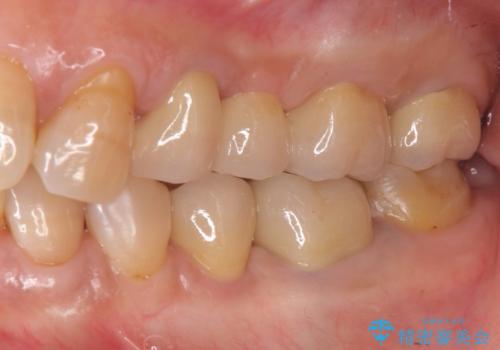

奥歯のインプラント治療

- 奥歯を失い噛めない、しっかりと噛めるようになりたいと希望され来院されました。

清掃性に優れたジルコニアカスタムアバットメント、ジルコニアクラウンを用いて機能性だけでなく審美性・予知性を高めます。

- 130万円(HAインプラント×3・骨造成・ジルコニアカスタムアバットメント×3・ジルコニアクラウン×4)費用は治療当時の料金となります